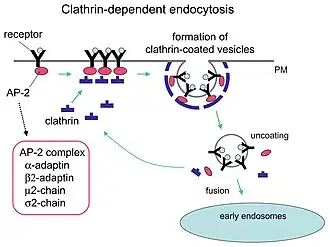

Vermehrungszyklus des HIV

Zur Vermehrung benötigt das Virus Wirtszellen, die den CD4-Rezeptor auf der Oberfläche tragen.[79] Dies sind vor allem CD4-tragende T-Helferzellen (CD4+-Zellen). Als hauptsächliches Reservoir für die humanen Immundefizienz-Viren dienen die follikulären T-Helferzellen in den Lymphfollikeln des Körpers, die rund zwei Prozent der CD4+-Zellen ausmachen.[80][81] T-Helferzellen unterstützen andere Weiße Blutzellen bei immunbiologischen Prozessen, wie der Reifung der B-Lymphozyten zu Plasma- und Gedächtniszellen oder der Aktivierung zytotoxischer T-Lymphozyten und Makrophagen. Neben T-Lymphozyten besitzen auch Monozyten, Makrophagen und dendritische Zellen CD4-Rezeptoren. Latent infizierte ruhende CD4+-T-Zellen (T-Gedächtniszellen) stellen langlebige Reservoire für HIV dar und sind der Grund, dass HIV trotz wirksamer antiretroviraler Medikamente bisher nicht eradiziert werden kann und es nach Absetzen der Therapie immer wieder zu Rezidiven kommt.[82][83][84]

Um mit der Zellmembran der Wirtszelle verschmelzen zu können, binden die Oberflächenproteine gp120 an die CD4-Rezeptoren. Durch die Bindung kommt es zu einer Konformationsänderung im Transmembranprotein gp41, ein Mechanismus, der einer „Schnappfeder“ oder einer „Mausefalle“ ähnelt.

Neben den CD4-Rezeptoren sind weitere Co-Rezeptoren an der Bindung des HI-Virus an weiße Blutzellen beteiligt:[85] Die Chemokin-Rezeptoren CCR5 an monozytären Zellen und CXCR4 an T-Zellen sind an der Bindung beteiligt.[86][87] Die unterschiedliche Ausprägung dieser Rezeptoren beeinflusst die Ansteckungswahrscheinlichkeit und den Verlauf der HIV-Infektion.[88] Moleküle, die die CCR5-Rezeptoren blockieren, gehören zur Wirkstoffgruppe der Entry-Inhibitoren, spielen in aktuellen HIV-Therapien jedoch eine untergeordnete Rolle.[89][90]

Im weiteren Verlauf folgt die Morphogenese, das heißt, über verschiedene Interaktionen finden die viralen Bestandteile wie Gag-, Pro-pol- und Env-Vorläuferproteine sowie die RNA zusammen und formen sich zu zunächst unreifen Virionen, die sich von der Plasmamembran abschnüren. Durch weitere Reifungsprozesse entsteht das reife Viruspartikel, bereit für die Infektion der nächsten Zelle. Zu den Reifungsprozessen gehört insbesondere die Spaltung der Vorläuferproteine – teils durch die virale Protease, teils durch zelluläre Enzyme – in ihre einzelnen Bestandteile, also von Gag in Matrix-, Kapsid- und Nukleokapsidprotein, Pol in Protease, Reverse Transkriptase mit RNase H und Integrase sowie Env in Oberflächen- und Transmembraneinheit. Die neugebildeten Tochtervirionen verlassen die Zelle durch Knospung. Beim Zusammenbau wird das HIV mit dem zellulären Protein Cyclophilin A bedeckt.[101] Dabei bindet je ein Cyclophilin A an zwei Hexamere des Kapsidproteins, wodurch es das Kapsid stabilisiert und maskiert vor intrazellulären Mechanismen der angeborenen Immunantwort in Makrophagen und dendritischen Zellen.[101]